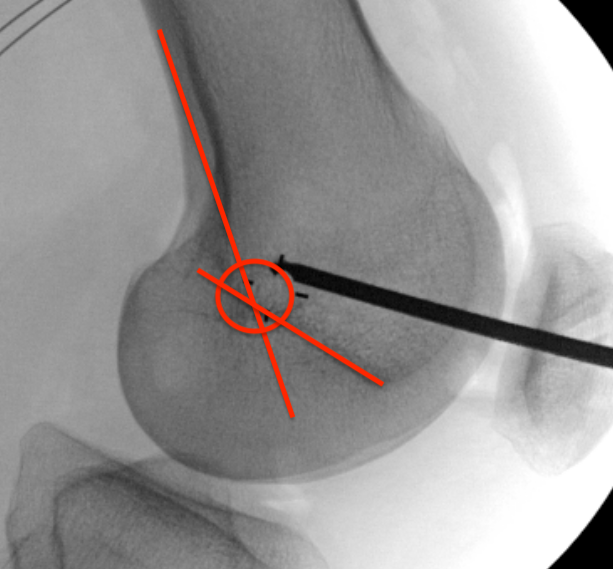

Femoral attachment

- 4 mm proximal and posterior to medial epicondyle

- image intensifier: intersection of the posterior femoral condyle with Blumensaat's line

- 40o anterior to avoid notch

- 40o proximal to avoid PCL tunnel

SchottleMCLMCL recon